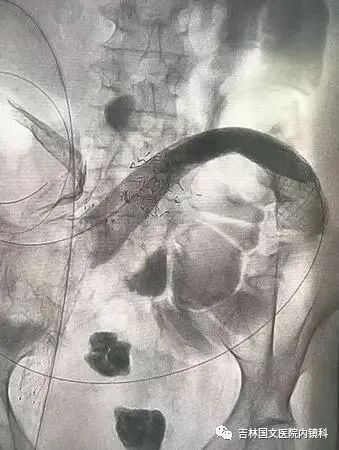

患者為結(jié)腸腫瘤致腸梗阻的病人,通過放置支架解除患者痛苦。手術(shù)開始,先置入導(dǎo)絲與導(dǎo)管,注入造影劑,顯示腸管走形,以確定狹窄段長(zhǎng)度及部位,見乙狀結(jié)腸狹窄,造影劑可通過,但導(dǎo)絲至結(jié)腸狹窄處通過失敗,候主任決定聯(lián)合內(nèi)鏡,進(jìn)行多學(xué)科合作。

邢主任迅速到達(dá),循腔進(jìn)鏡至乙狀結(jié)腸腫瘤處,見腫瘤環(huán)形生長(zhǎng),腫瘤似豆腐渣樣脆弱又霸道的侵占著本來就不寬敞的路,中指一樣粗細(xì)的腸鏡是無法通過了,只能做一盞指路的明燈,帶領(lǐng)導(dǎo)絲駛?cè)肽康牡?,在邢主任富有?jīng)驗(yàn)的操作以及候主任隨機(jī)應(yīng)變地配合下,整個(gè)操作行云流水,導(dǎo)絲終于順利通過,送檢病理后,退出腸鏡。

又經(jīng)過一系列操作,腸道支架順利置入,患者術(shù)后排出大量稀便及氣體,腹脹明顯緩解,解決了患者的生理難題,提高了生活質(zhì)量。